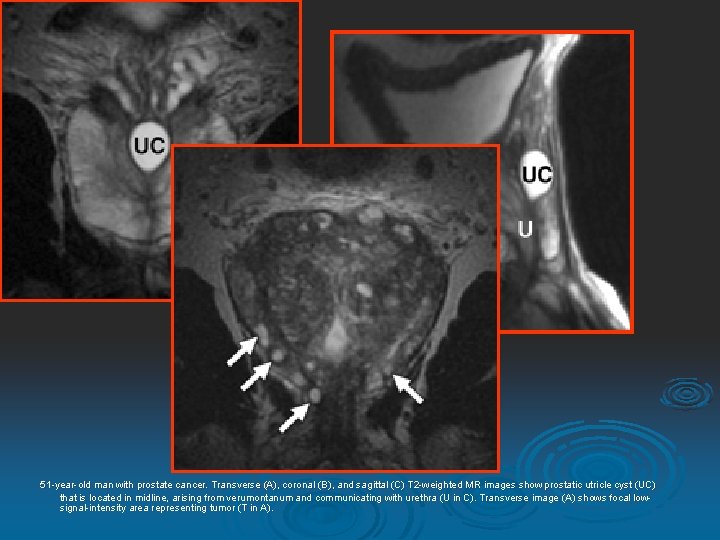

51 -year-old man with prostate cancer. Transverse (A (A), coronal (B (B), and sagittal (C (C) T 2 -weighted MR images show prostatic utricle cyst (UC) that is located in midline, arising from verumontanum and communicating with urethra (U in C). Transverse image (A (A) shows focal lowsignal-intensity area representing tumor (T in A).